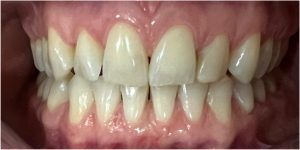

Przeprowadziliśmy precyzyjne leczenie implantologiczne, wszczepiając 11 implantów w szczęce i żuchwie. Konieczna była też regeneracja kości. Po 6 miesiącach gojenia nastąpiła odbudowa pełnołukowa. Kształt, kolor i ustawienie zębów zostały dobrane oraz wykonane na indywidualne życzenie Pacjenta.

Leczenie chirurgiczne i implanto-protetyczne przeprowadził lek.stom. Michał Badowski.